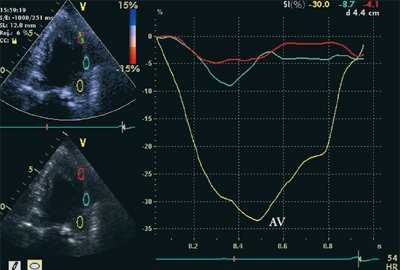

На рис. 3-5 приведены различные варианты ПСУ у больных с постинфарктным кардиосклерозом.

"Седловидная" и "ступенчатая" формы движения обусловлены наличием постсистолического смещения миокарда, превышающего по амплитуде максимальное систолическое смещение.

![Кривые деформации миокарда в норме]()

![Кривые деформации миокарда при постинфарктном кардиосклерозе]()

б) При постинфарктном кардиосклерозе. У больного регистрируется высокоамплитудный пик постсистолической деформации (STps).

Вертикальная линия (AV) на рис. 3-5 соответствует времени закрытия аортального клапана. На представленных графиках также отмечается наличие базально-верхушечного градиента (снижение пиковых миокардиальных скоростей, продольного систолического смещения и деформации от основания к верхушке левого желудочка).